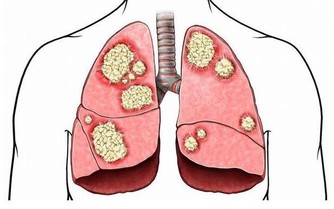

三、在抬腳時可引濁氣下行排出,升清降濁正氣倍增,體內正常細胞大曾活躍,癌細胞自然死亡。